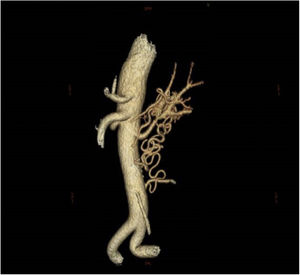

La angio-TC mostró una estenosis crítica en el tercio medio de la arteria renal izquierda, con una malformación vascular en forma de ovillo en el hilio renal que se extendía caudalmente con numerosas colaterales que unían las arterias vertebral y mesentérica (fig. 2) con retraso de la perfusión en fase arterial y venosa del riñón izquierdo respecto al riñón contralateral.

No se encontraron lesiones ateroscleróticas en la angio-TC. Tampoco cumplía los criterios de arteritis de Takayasu u otros tipos de vasculitis, ni había presentado ningún traumatismo local. Por estas razones, se sugirió que el origen de la estenosis de la arteria renal y la maraña vascular era de origen malformativo.